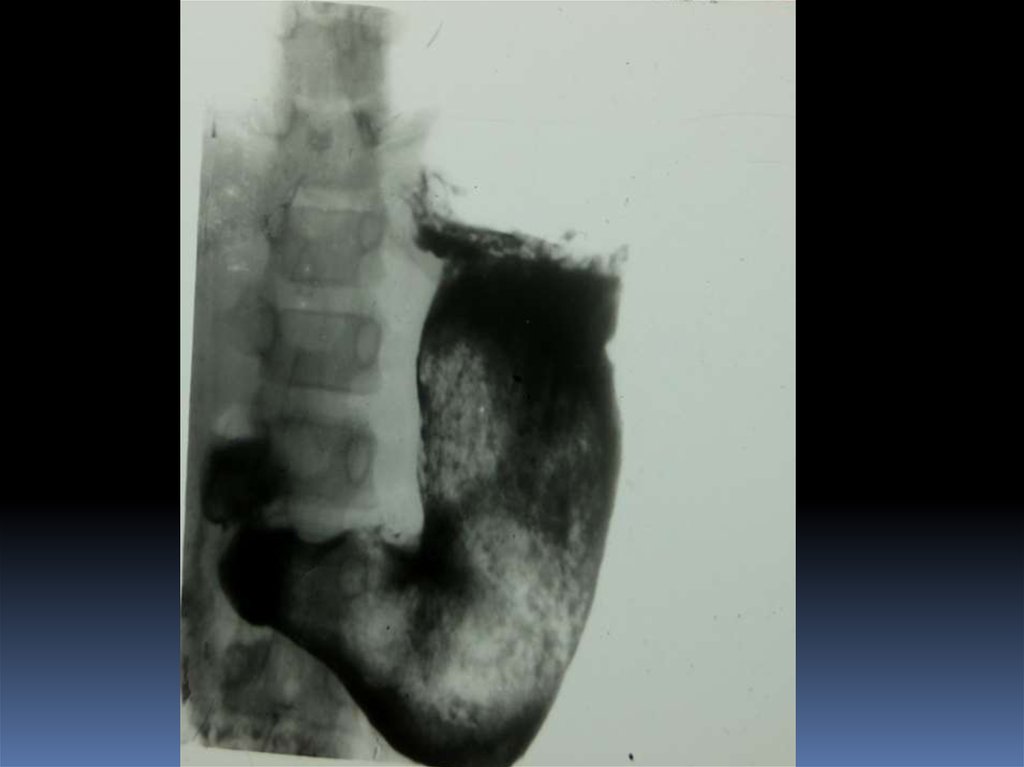

16. Рентгенодиагностика рака желудочно-кишечного тракта

Рентгенодиагностика

рака желудочнокишечного тракта

17. Классификация рака органов ЖКТ

1. Экзофитная форма:

2. Эндофитная форма:

узловая форма;

диффузноинфильтративная

форма;

полипоподобная

чашеподобная форма. инфильтративноязвенная.

3. СМЕШАННАЯ ФОРМА – 10-15%